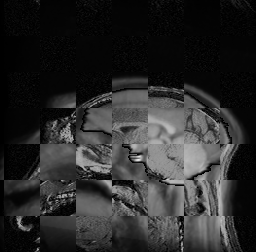

For each of the 10 subjects, we show checkerboard slices in each direction (1) before registration, first row; (2) after rigid->scaleversor->affine registration, second row; and (3) after BSpline registration, third row.

Calvin